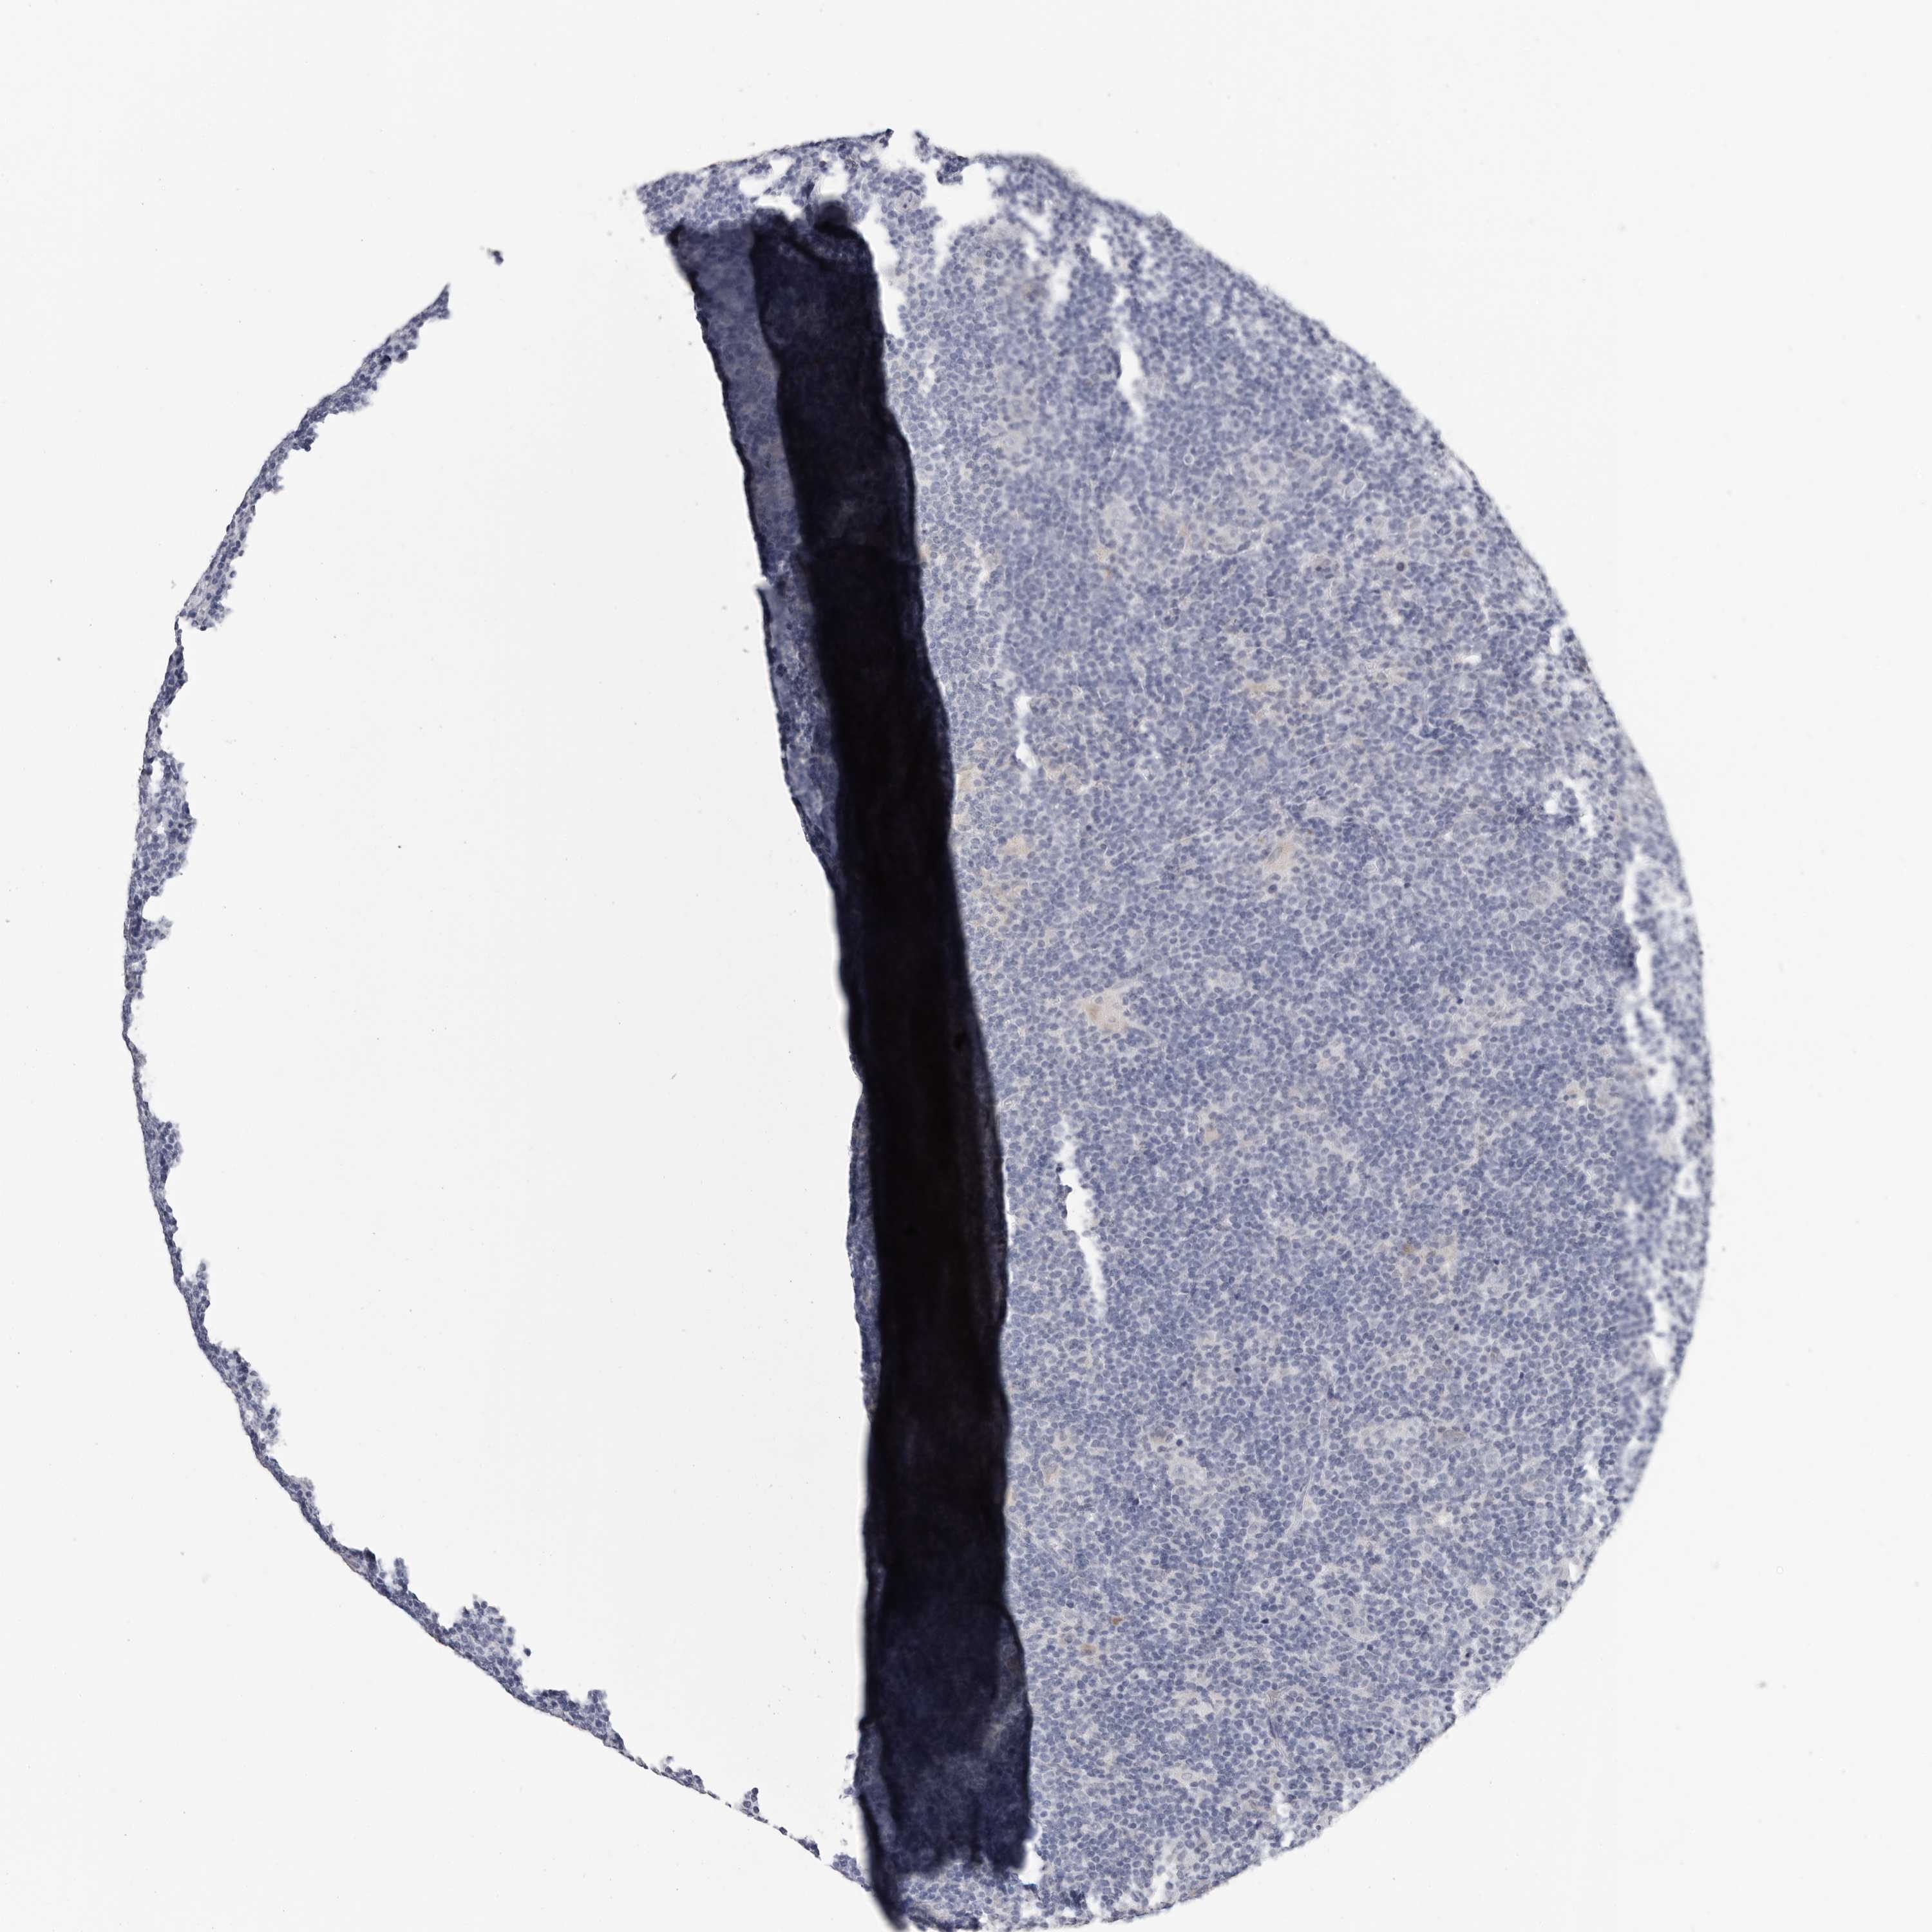

LYMPHOMA - Protein expressioni

A mouse-over function shows sample information and annotation data. Click on an image to view it in a full screen mode. Samples can be filtered based on level of antibody staining by selecting one or several of the following categories: high, medium, low and not detected. The assay and annotation is described here.

Antibody staining in the annotated cell types in the current human tissue is reported as not detected, low, medium, or high, based on conventional immunohistochemistry profiling in selected tissues. This score is based on the combination of the staining intensity and fraction of stained cells.

Each image is clickable and will lead to virtual microscopy that enables deeper exploration of all samples and also displays staining intensity scores, fraction scores and subcellular localization as well as patient and tissue information for each sample.

Antibody HPA029557

Hodgkin's disease, NOS

Malignant lymphoma, non-Hodgkin's type, High grade

Malignant lymphoma, non-Hodgkin's type, Low grade